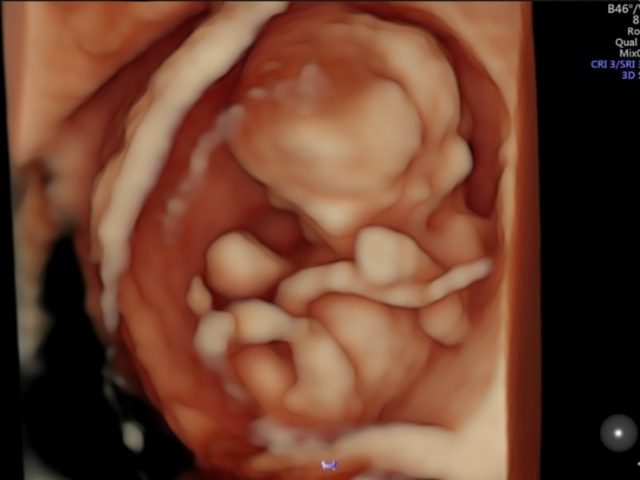

Siêu âm không phải là hoàn hảo và thần thánh như nhiều người tưởng mà có nhiều hạn chế về mặt kĩ thuật, Siêu âm không nhìn rõ được thai trong bụng mẹ giống như ta trực tiếp nhìn em bé đã được đẻ ra rồi, bế trên tay xoay và lật mọi phía để xem em bé. SIÊU ÂM KHÔNG BIẾT HẾT ĐƯỢC BỆNH TẬT CỦA THAI. Có một số vấn đề ảnh hưởng đến độ rõ nét của hình ảnh siêu âm như: Tư thế thai nằm không thuận lợi, khuất sau xương chậu mẹ, buồng tử cung của mẹ quá chật bó sát người thai như quấn chăn che kín suốt từ đầu đến chân – không có khoảng trống để xoay, đề cử động. Mẹ có vết mổ đẻ cũ. Mẹ có thành bụng dày mỡ. Da bụng mẹ quá dày, xơ cứng. Người mẹ không đi siêu âm thai định kì, bỏ qua những tháng quan trọng, bỏ qua những mốc thời gian quan trọng để phát hiện một số dị tật đặc thù. Những dị tật rất khó, không phát hiện dược trên siêu âm ví dụ như: Tật dính ngón, bất thường ngón. Không sứt môi nhưng có hở hàm ếch. Không có lỗ tai. Hẹp hay không có lỗ hậu môn. Các tổn thương phẳng mặt da như các bớt, vết chàm, các khối u phẳng hay hơi lồi hơn mặt da 1 chút. Bất thường rãnh não nhỏ…v..v…

Sự thật là: Siêu âm không thể phát hiện được hết dị tật của thai mà chỉ phát hiện được tối đa 70% dị tật mà thôi (đó là đối với bác sĩ giỏi, có kinh nghiệm và cẩn thận, tư thế nằm của thai thuận lợi, dạ con của mẹ không quá chặt, da bụng mẹ không quá dầy mỡ, không có sẹo mổ đẻ cũ, mẹ đi siêu âm thai định kì hàng tháng, máy siêu âm tốt… còn nếu không thì tỉ lệ phát hiện dị tật còn thấp hơn nhiều) SIÊU ÂM KHÔNG BIẾT HẾT ĐƯỢC BỆNH TẬT CỦA THAI.